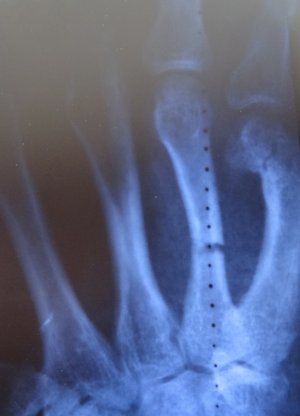

Доктор сказал что сращения нету вообще, опять наложилли лонгету и сказал ходить ка минимум еще две недели только согнули пальцы немного под углом и уже на 3,4 и 5 палец плюс назначил магнитотерапию (вроде так, точно не помню) , вот фото лонгеты: